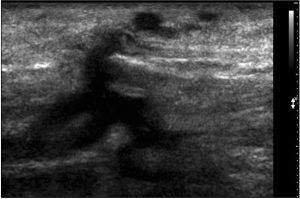

Лечение несафенозного рефлюкса индивидуально и зависит от тяжести симптомов. Требуется тщательное планирование и УЗИ-контроль. Из-за извилистости и поверхностного расположения несафенозных вен, методы, такие как РЧА и ЭВЛК, ограничены. Предпочтение отдается пенной склеротерапии и флебэктомии. При тазовых венах без симптомов используется пенная склеротерапия под контролем УЗИ или флебографии (техника «снизу вверх»), а при симптомах или рецидиве — с пеной и спиралями (техника «сверху вниз»).

Протяженность рефлюкса в несафеных венах можно выявить, проследив за варикозными венами в разных местах. Эти вены не входят в стандартное дуплексное сканирование, что может привести к неправильному диагнозу и выбору тактики лечения. Повышение осведомленности и углубления понимания рефлюкса в несафенных венах улучшит диагностику и лечение. Это несомненно положительно скажется на результатах лечения варикозной болезни.